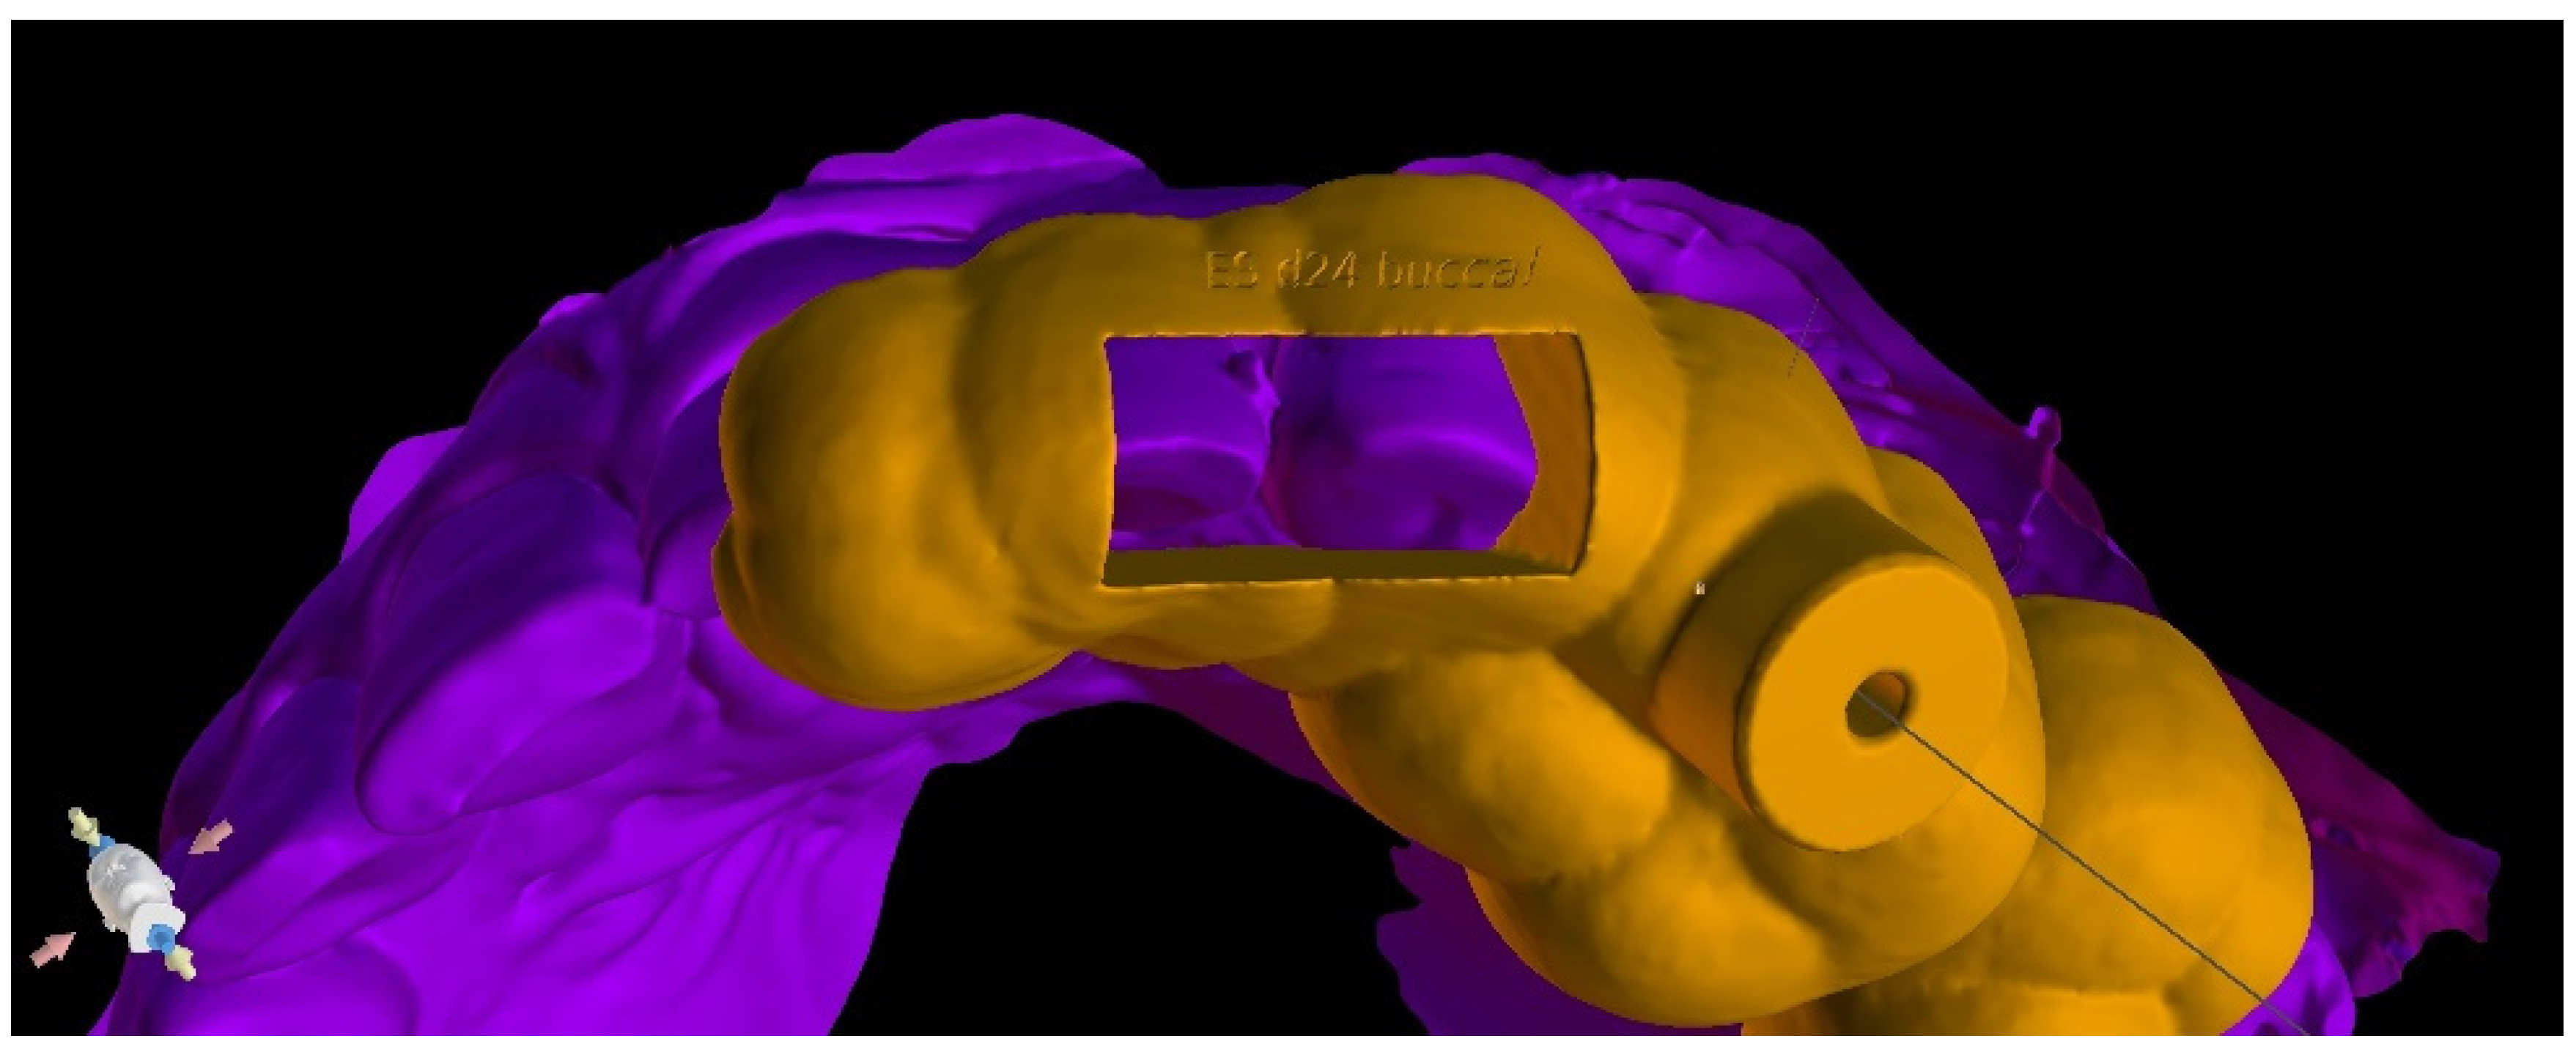

Three-Dimensional Treatment Plan

Three-Dimensional Treatment Plan and RCT

| Design the virtual drill path and the endodontic guide |

| Three-dimensional printing |